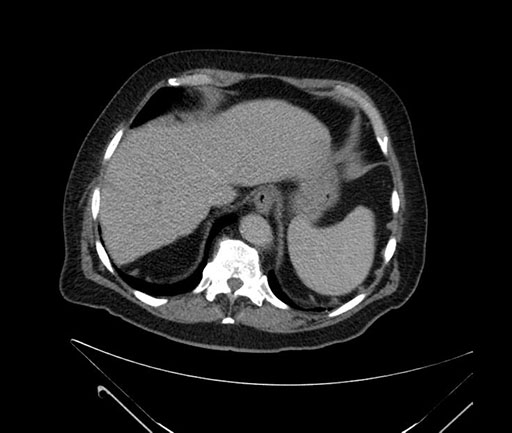

Imaging Analysis

Look through the patient's CT scan to identify any areas of concern for the necessary procedure.

Based on your CT findings, which issue(s) would give reason for "planned slowing down moment(s)" in this case?